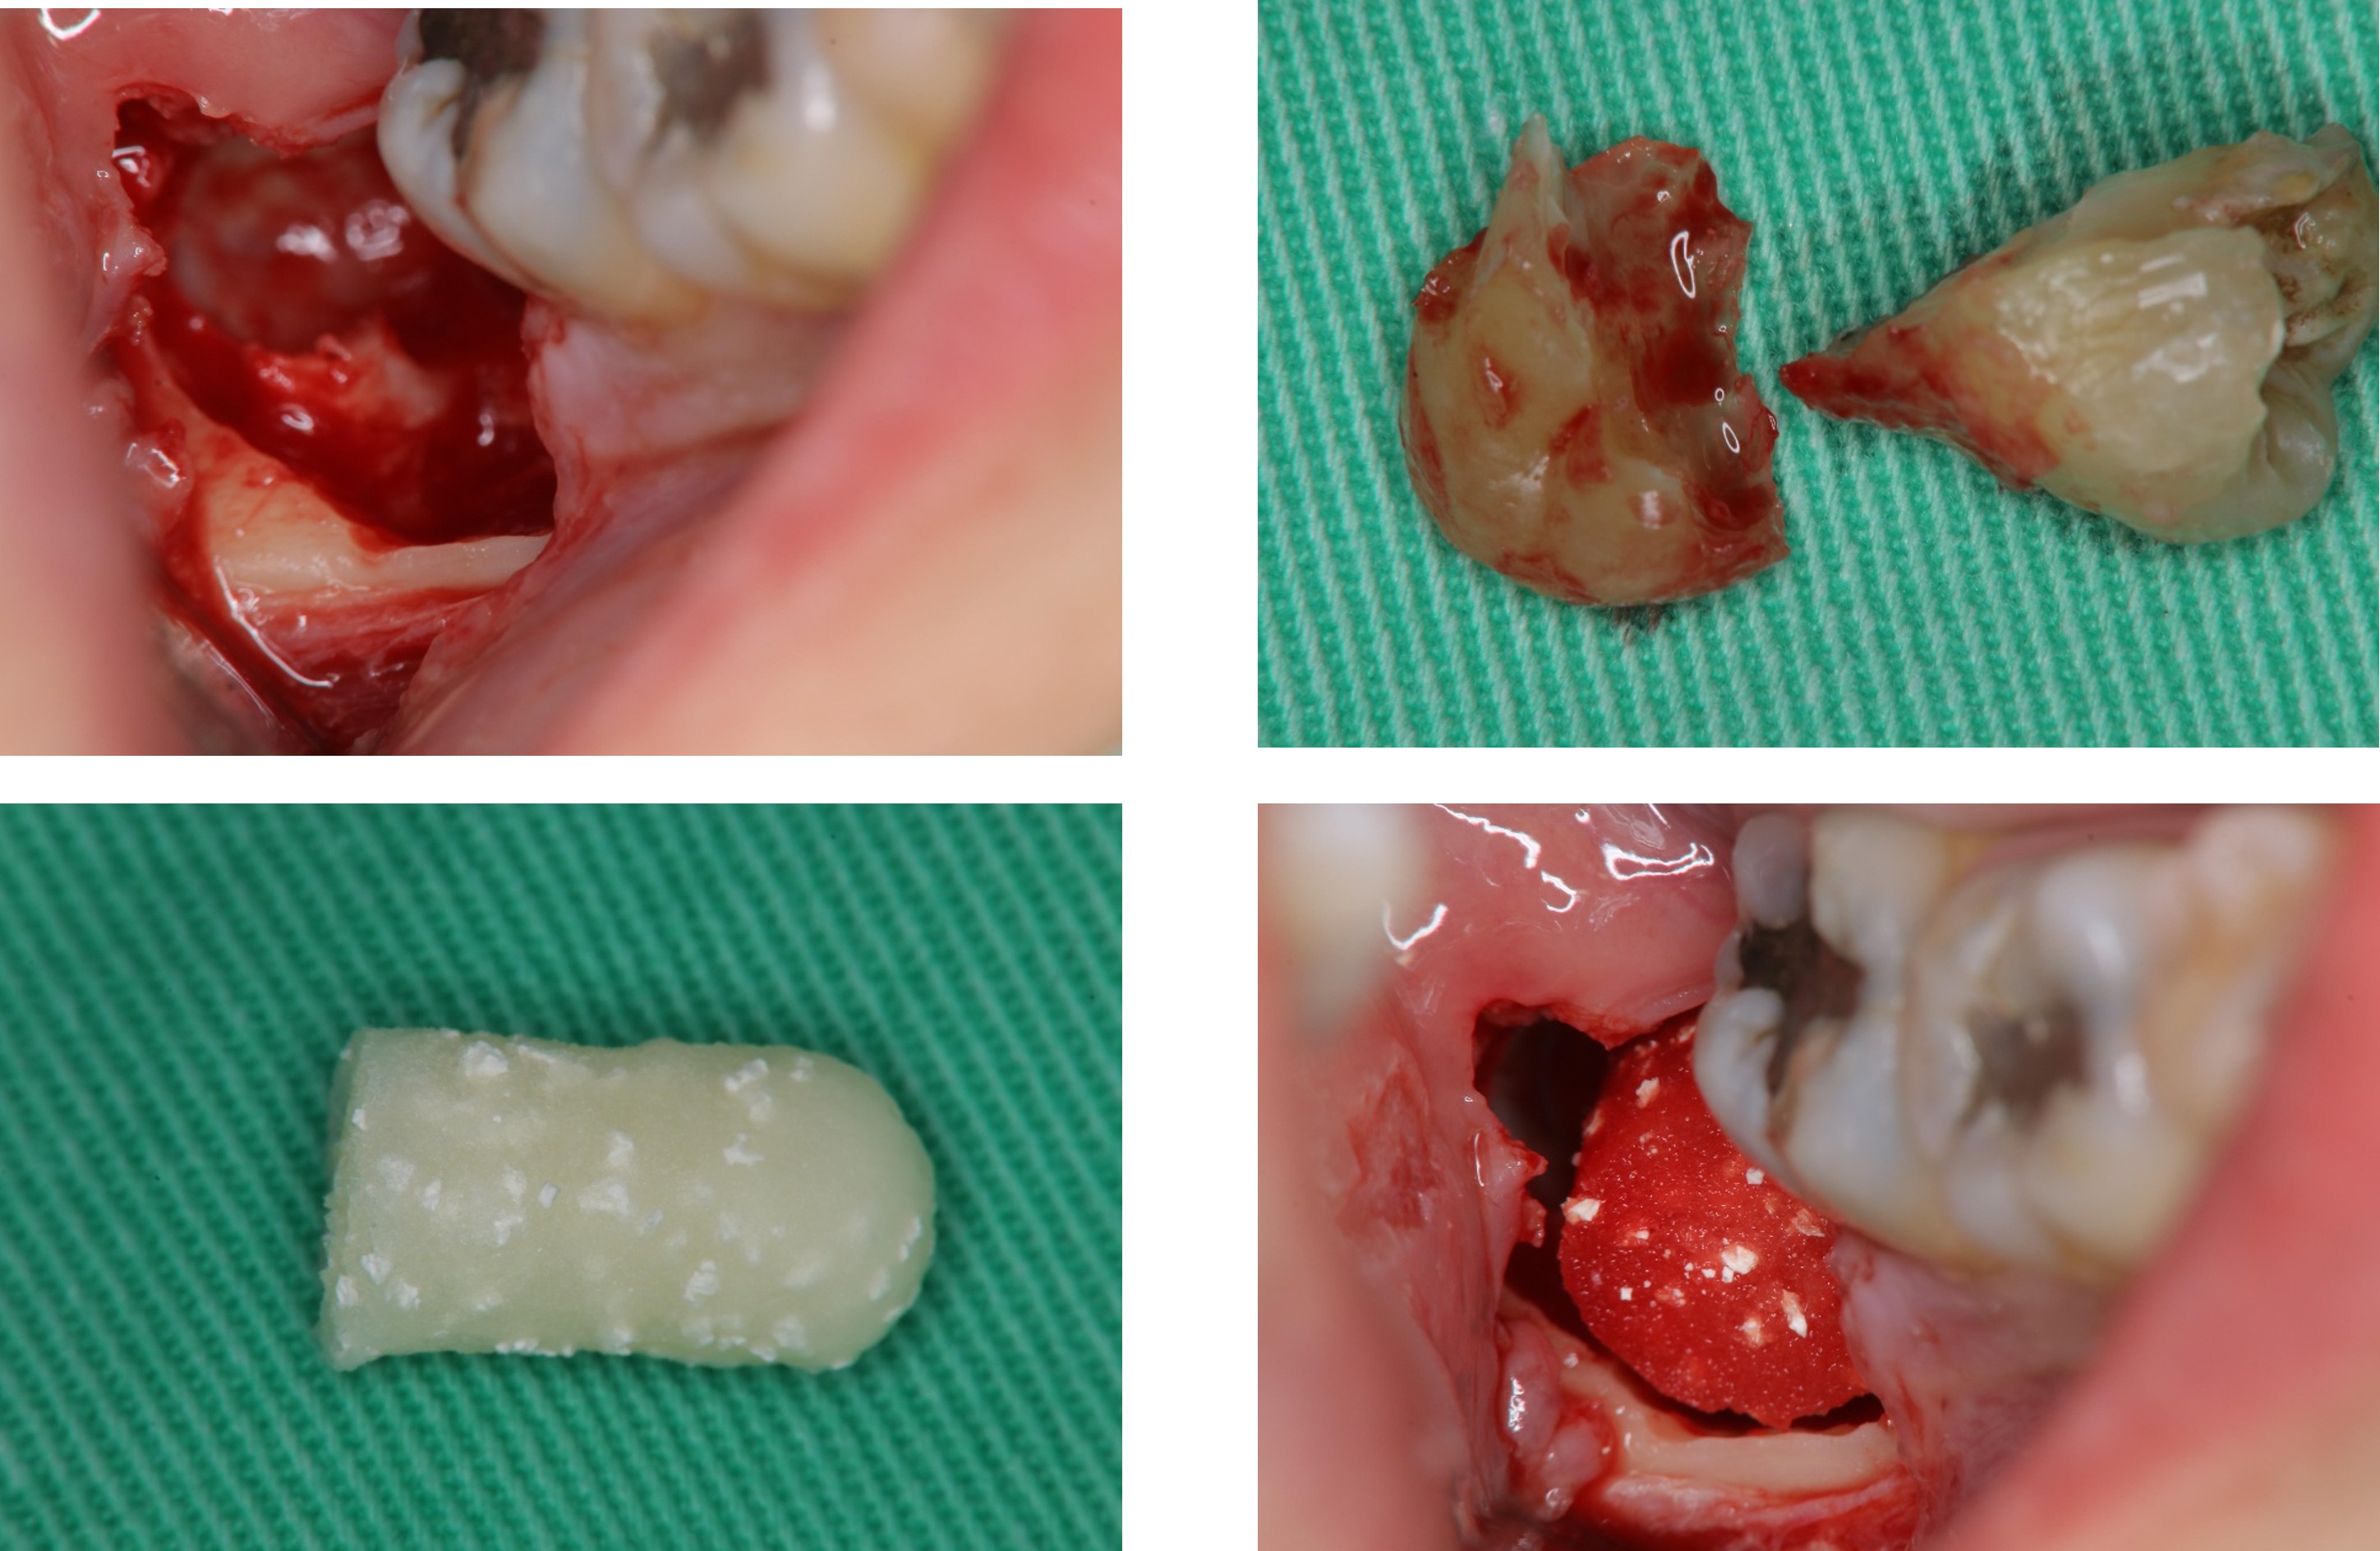

1週後傷口癒合良好

使用骨質增生膠原蛋白,來處理拔牙後的傷口。此材料適用的範圍不僅用於拔牙後傷口,所有顎骨中的病灶於手術後皆建議使用。

骨質增生膠原蛋白優點:

1 、止血效果:特殊生物材料,能立即止血,且無血塊脫落之困擾。

2、減痛效果:加速傷口癒合,有效減輕疼痛

3 、預防效果:健全牙周組織,避免鄰近牙齒產生牙周病及乾性齒槽炎